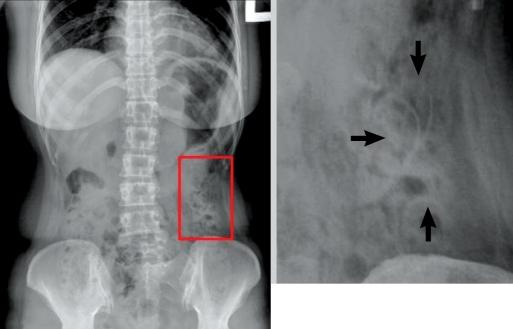

Foreign bodies in the gastrointestinal tract often cause serious complications, such as perforation, obstruction, abscess formation, or hemorrhage. This is a case in which a patient visited our hospital and complained of a vague lower abdominal pain that had been present for three months. She had an intrauterine device (IUD) inserted five years earlier. The abdominal X-ray, computed tomography and colonoscopy revealed that the IUD had penetrated into the descending colon. We tried to remove the IUD by colonoscopy but failed due to pain, so we removed the IUD surgically. Thus, we report a case in which a previously inserted IUD had penetrated into the descending colon and was surgically removed. We also present a brief review of the literature.